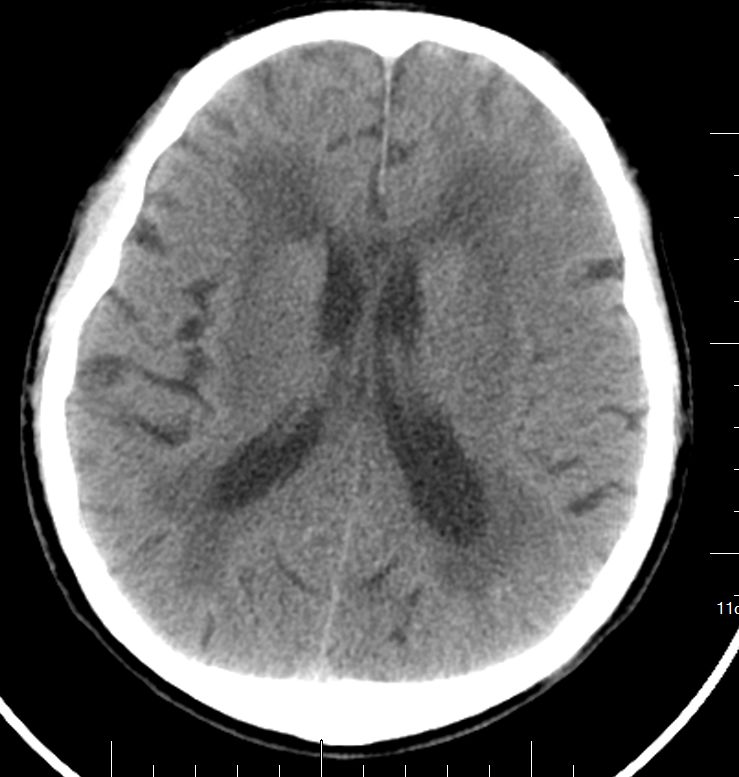

既往有高血压病史,血压控制不详。急诊头颅 CT:颅内多发缺血腔梗灶。

两侧半卵圆中心、右侧基底节区多发缺血腔梗灶